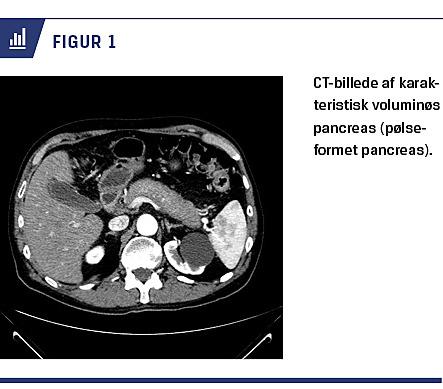

Ved billeddiagnostik ses der hos 40-60% af patienterne typiske forandringer, som karakteriseres af diffus forstørrelse af hele pancreas og forsinket opladning. Dette kaldes også en pølseformet pancreas (Figur 1). Hos 12-40% ses der endvidere en kapsellignende afgrænsning mod det omkringliggende væv – en halo. Atypiske forandringer ses hos 30-40% og kan være enten fokale eller multifokale. Oftest er disse forandringer lokaliseret til caput pancreatis og kan til tider være svære at differentiere fra pancreascancer. Endelig vil der være karakteristisk opladning i de forskellige faser. Ovenstående kan visualiseres ved CT, MR-skanning og PET [5, 19, 20]. UL-skanning af abdomen er mindre specifik, men kan dog bruges til påvisning af en hypoekkoisk diffus forstørret pancreas [5].